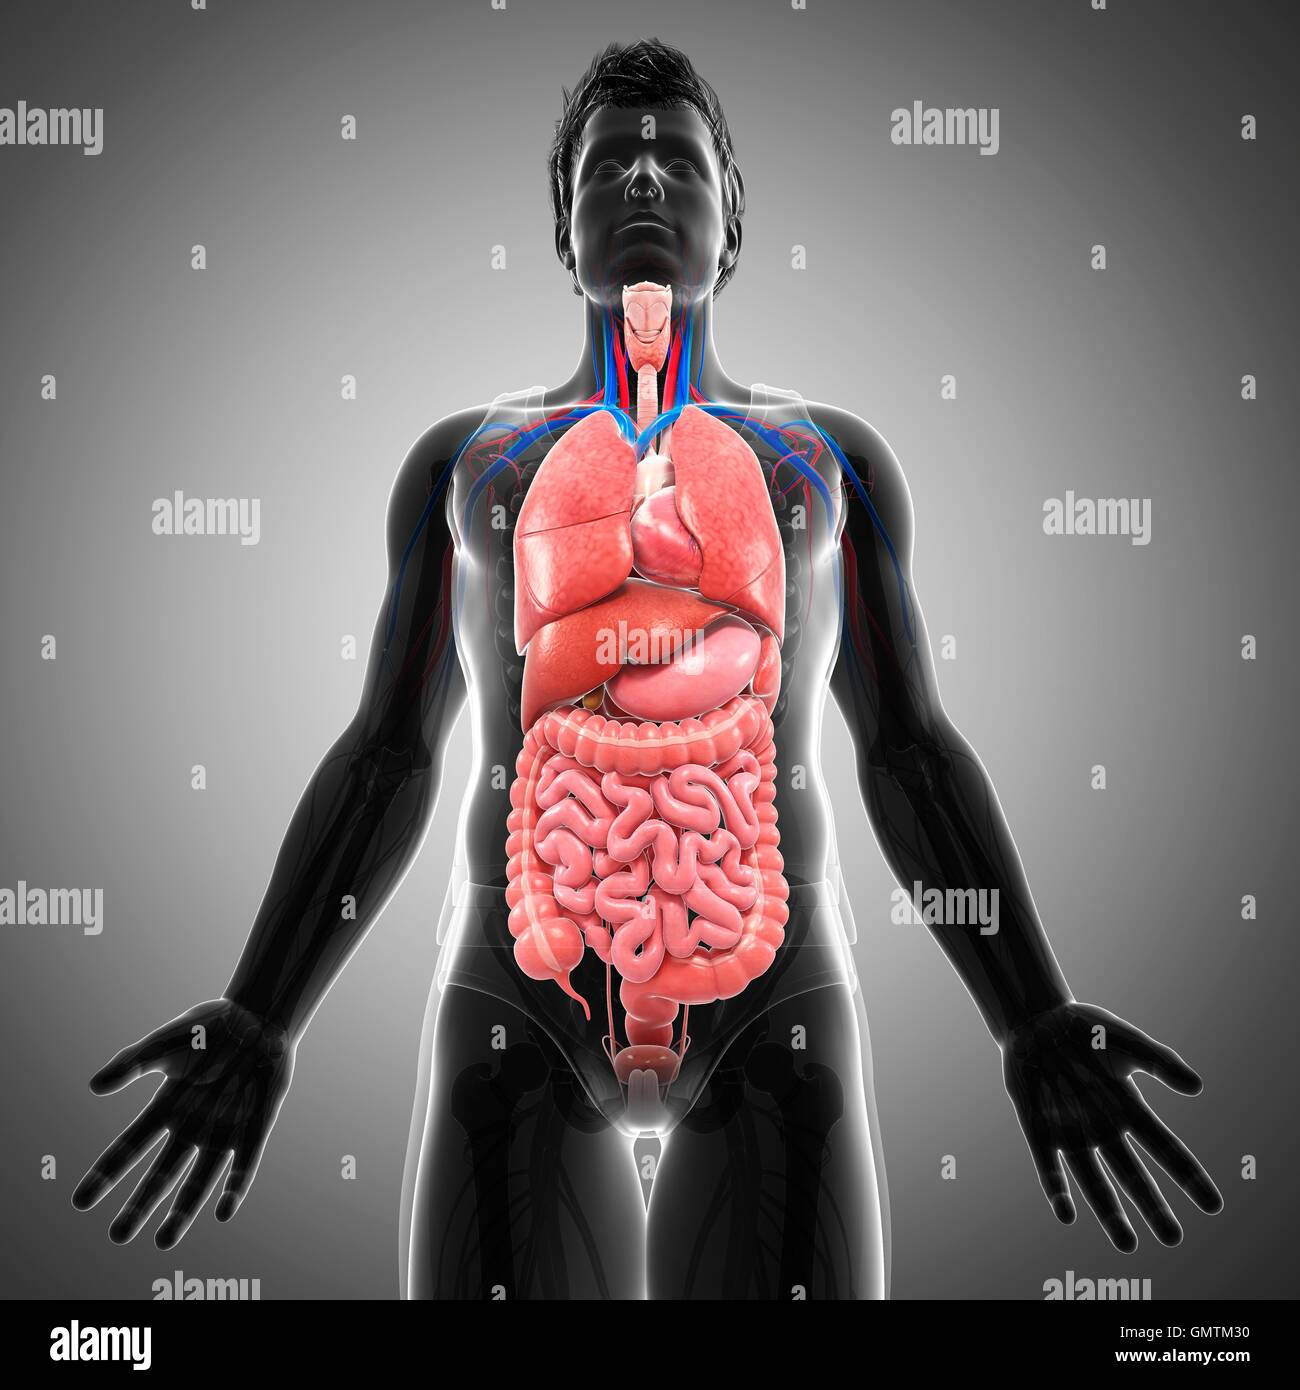

Human Male Organ Locations Person persons eg she s an interesting person people there are so many people travelling here people peoples

Human Male Organ Locations

Human Male Organ Locations

Transparent Body Model Showing Male Anatomy And Internal Organs

Male Internal Organs Anatomy Stock Photo Alamy

Human Body Organs Diagram Male

Male Internal Organs Anatomy Stock Photo Alamy

Human Male Organ Locations - [desc-13]